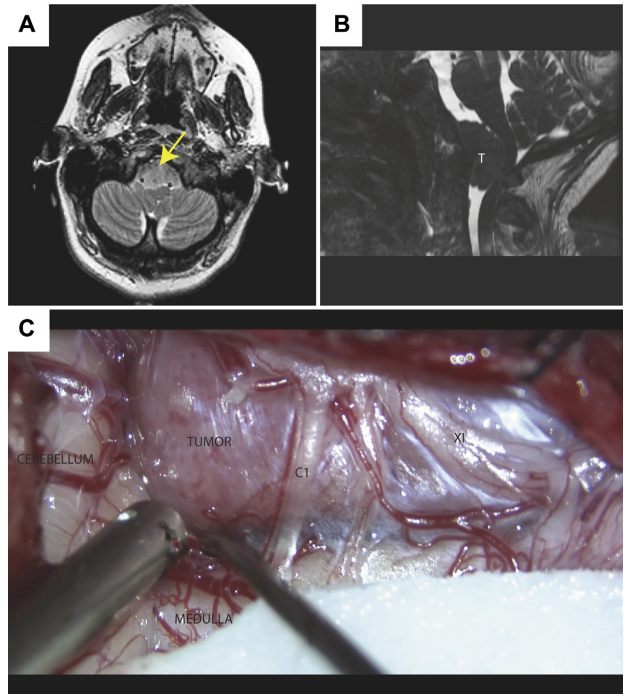

怀孕期间诊断出枕骨大孔区脑膜瘤怎么办?一位34岁的女性患者,在她的妊娠中期确诊脑膜瘤,经原外侧入路成功切除。...